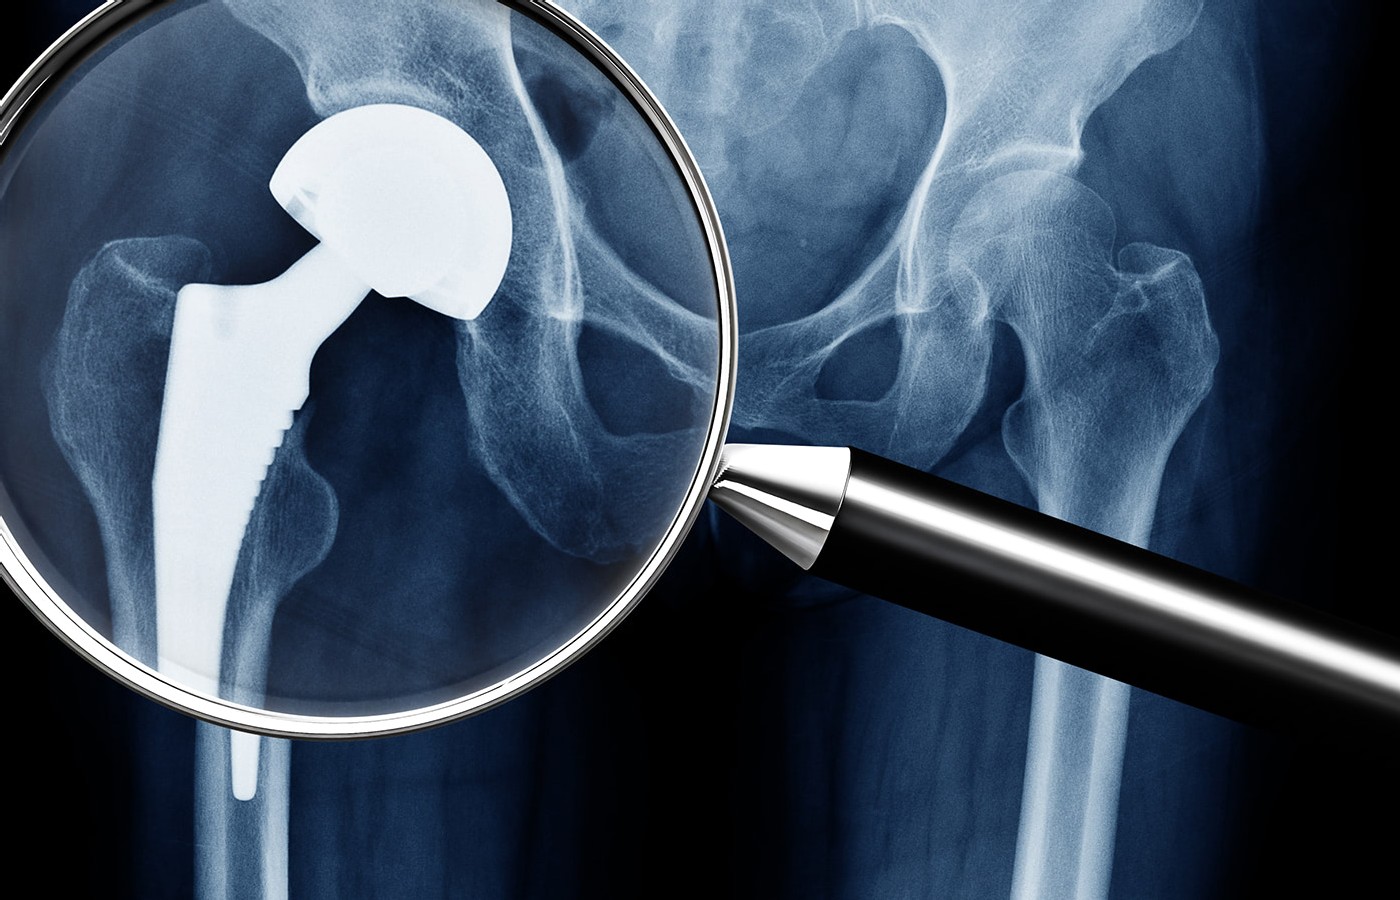

Spotting Heterotropic Ossification

- Heterotropic ossification can become a serious, debilitating complication after total hip replacement.

- Health care providers need to be aware of this complication; especially those of us who treat musculoskeletal disorders.

- Often HO presents as an incidental finding on plain radiograph. The heterotopic bone typically forms in the connective tissue between the muscle planes around the femoral neck and adjacent to the greater trochanter.

HO After Hip Replacement

HO can become a serious, debilitating complication after total hip replacement. (Fig. 1) The incidence of HO after total hip arthroplasty (THA) varies widely from 15% to 90% depending on the patient population. The consensus is that the incidence of HO is about 53% in THA, with one-third of cases clinically significant.1-3